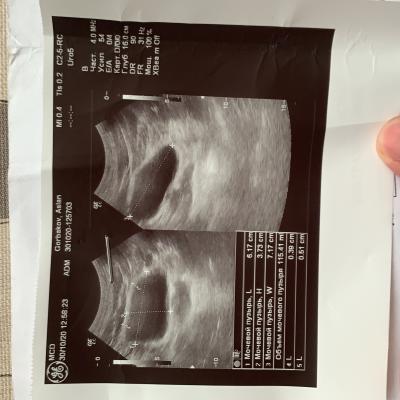

Застудил ноги, начал бегать в туалет, пошел в больницу, поставили диагноз хрон простатит и начали лечить, , лечили толку нет и после этого началась струя в разные стороны, сменил врача — то же самое, лечили простату. Мочевой не смотрели. Думали стриктура — сделали уретроцистоскопию, ее нет. Была чуть воспалена шейка. Сейчас обнаружили зппп, вылечили. Их нет. Симптомы остались, воспаления сняли. В узи выявили какую-то лунообразную впадину. Посмотрите пожалуйста, назначили лидазу/дистрептазу и амикацин. Анализы все чистые, флоры нигде нет.

Здравствуйте! По данным приведенных результатов обследования - имеет место хронический урогенитальный воспалительный процесс с проявлениями дисбиоза, с возможной более высокой концентрацией enterobacteriaceae/enterococcus в секрете простаты и эякуляте. Также - имеют место диффузные изменения предстательной железы с тенденцией к увеличению объёма простаты. Необходимо сделать бакпосев эякулята с определением чувствительности к антибактериальный препаратам( но не ранее, чем через месяц после последнего приёма любого антибактериального препарата по любому поводу). Для защиты предстательной железы, можно рекомендовать комплекс Гардапрост, который способствует остановке роста и деления клеток предстательной железы, уменьшению выраженности воспаления, уменьшению разрастания соединительной ткани в предстательной железе. Удачи!